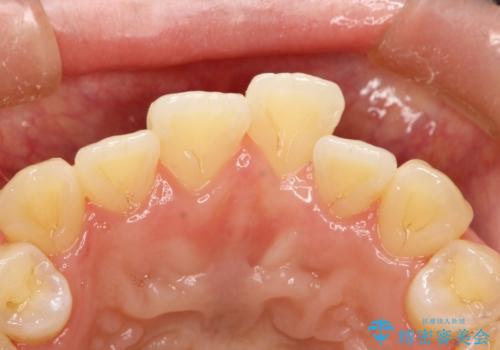

- 全体の歯にうっすらと茶渋によるステインが見られます。

よく見ると歯自体はあまり黄色くないので、ステインによって歯が黄色く見えてしまっています。

PMTCというクリーニングを行うことでステインは除去できるので、今回はPMTC(エアフロー)の60分コースにて全体のクリーニングを行いました。